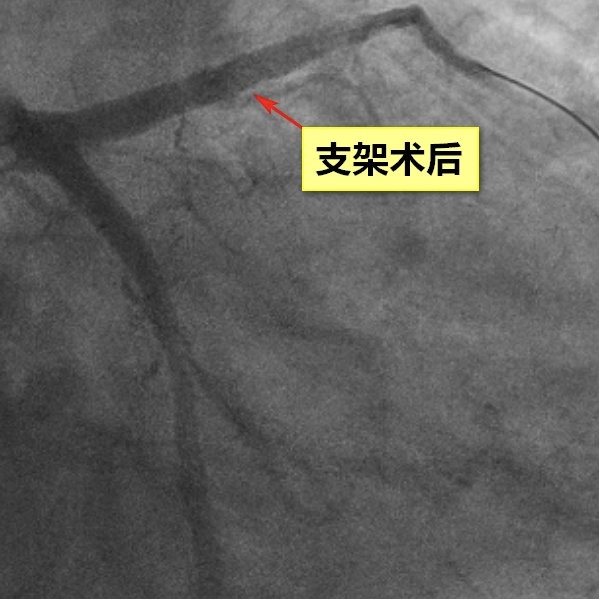

在医护团队高效协作下,患者被迅速转送至导管室,为抢救争取了宝贵时间。胸痛中心多科室高效联动,急诊介入手术迅速开展。从患者进入急诊科至导丝通过闭塞血管(前降支),仅用时40分钟,远低于国家胸痛中心90分钟的标准,实现了迅速血运重建,最大程度挽救了濒危心肌。这一过程充分体现了“时间就是心肌,时间就是生命”的急救理念,也彰显了医院胸痛中心在急危重症心血管疾病救治中的专业能力和协同效率。